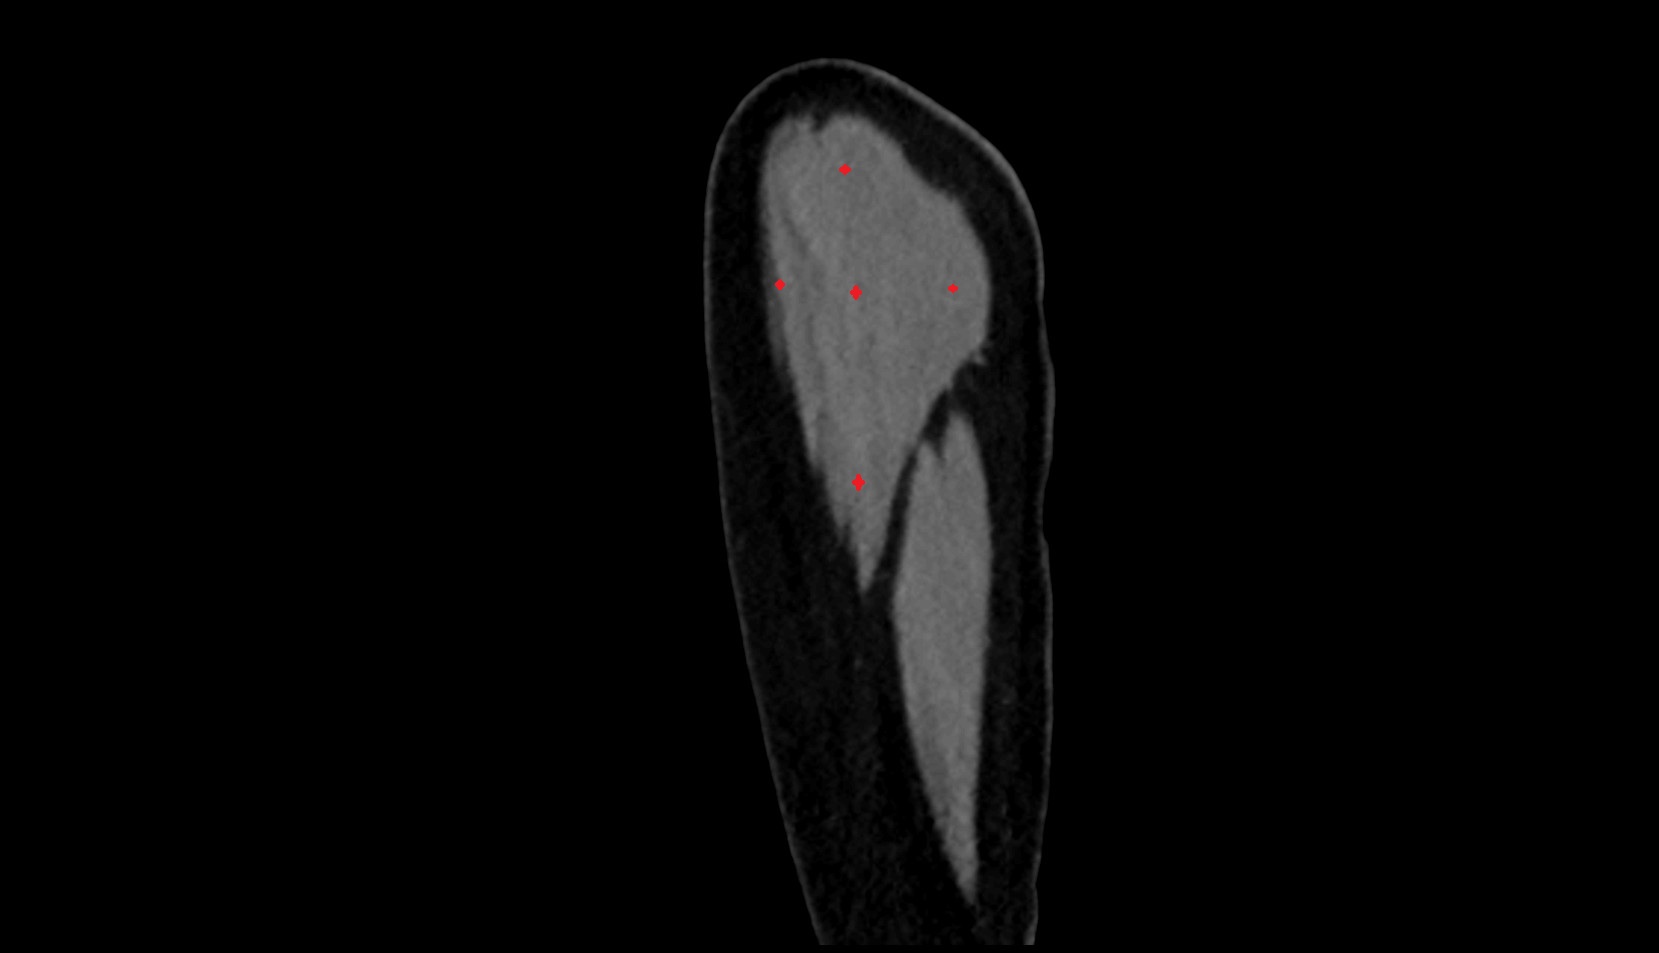

- Deltoid muscle

- Biceps brachii muscle

- Triceps brachii muscle

- Shoulder joint (glenohumeral joint)